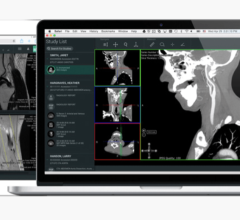

Vital Images at RSNA will be featuring Vitrea Enterprise Suite, which combines the company’s powerful 2D, 3D and 4D clinical applications and services with a centralized solution for managing volumetric image data across the medical enterprise. The centralized data management solution, called Vital Image Management System (VIMS), delivers universal access to a single source of imaging data across the medical enterprise.

The suite addresses the challenge of managing multiple, disparate advanced visualization systems. Because Vitrea Enterprise Suite does not require proprietary hardware, customers can leverage their existing infrastructure. In addition, customers can select deployment options to meet the unique needs of their clinical environments – via Web browser, a stand-alone workstation, integrated into a PACS, or via an electronic medical records (EMR) or hospital information management system.

Vitrea Enterprise Suite also includes the company’s award-winning services – support, education, and integration and implementation consulting.